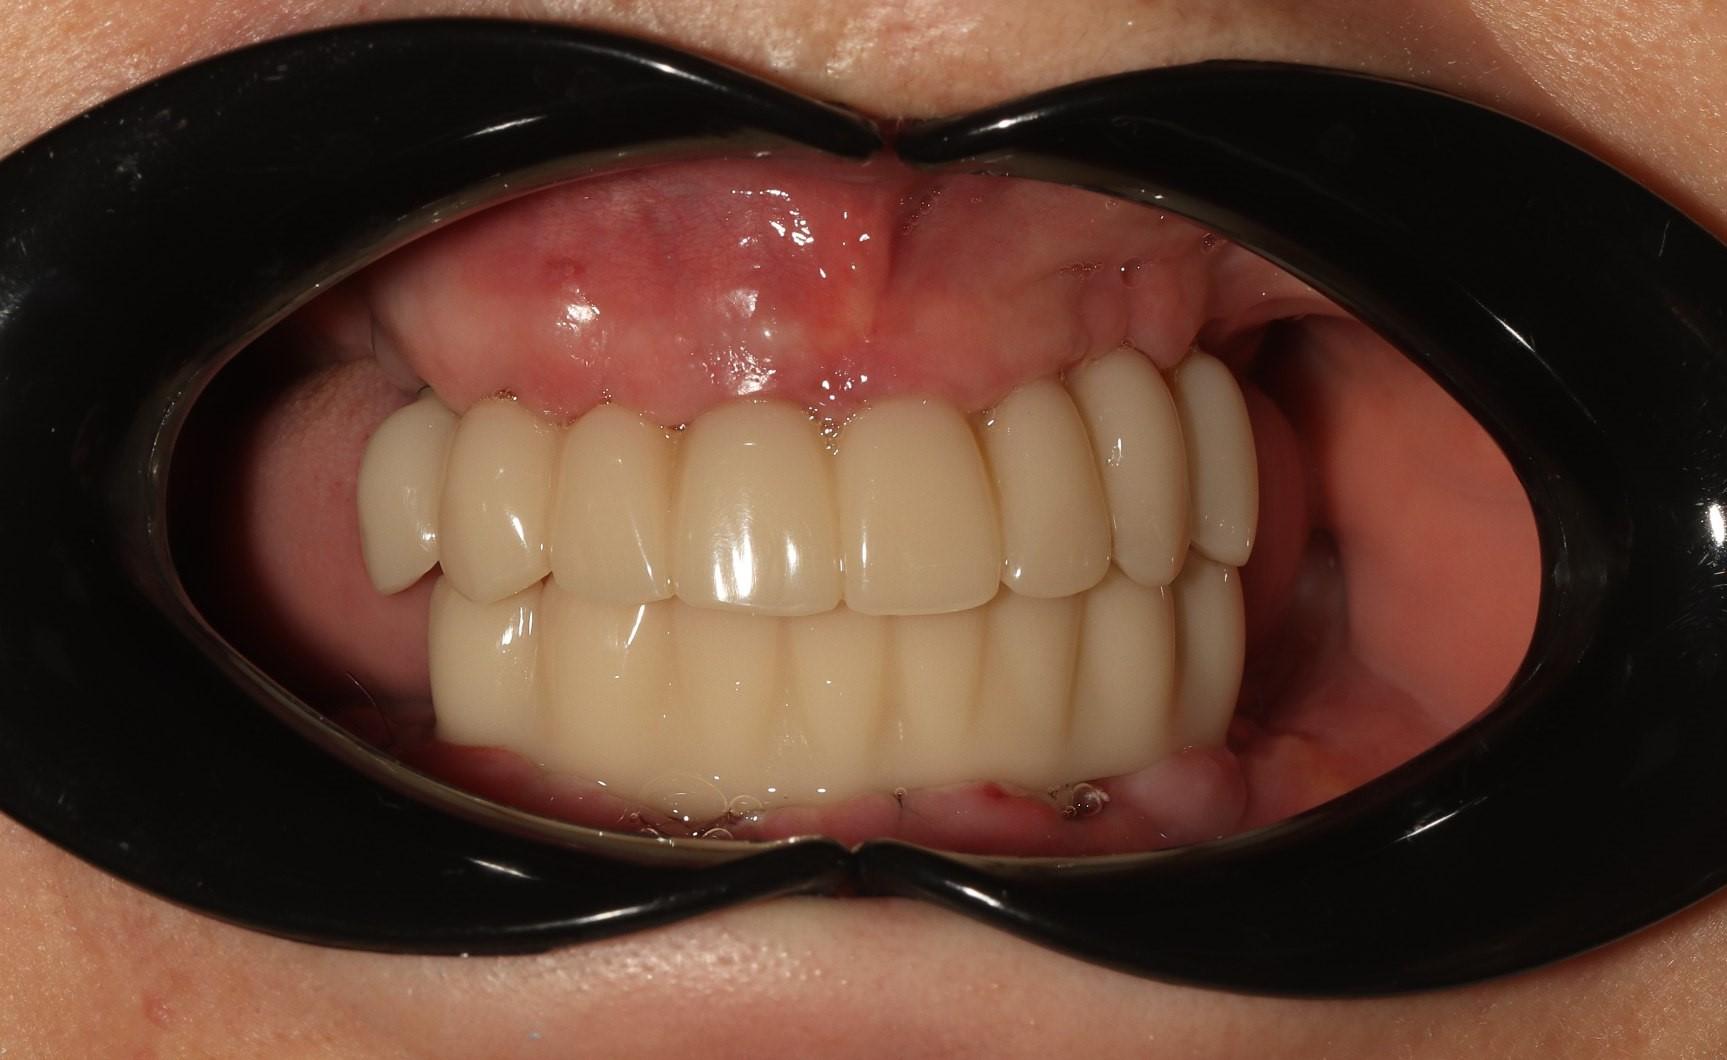

before

after